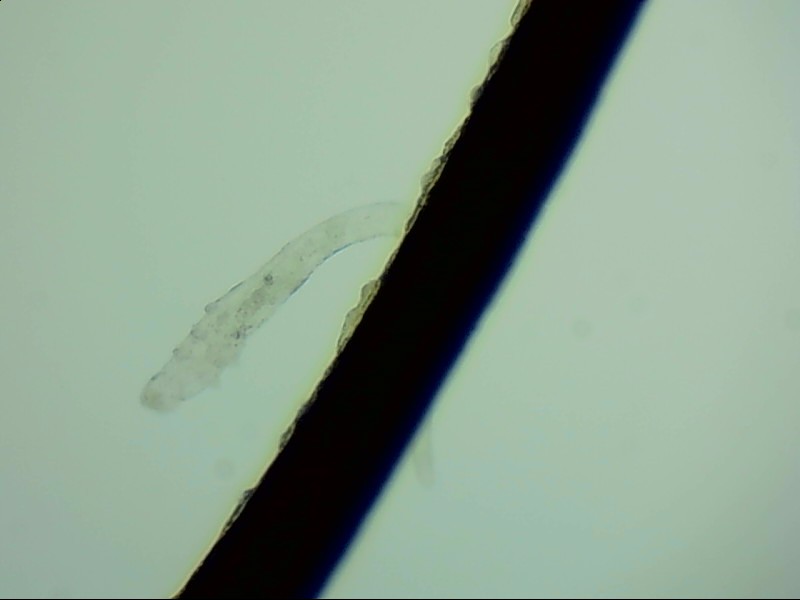

小張是一位程序員,長(zhǎng)時(shí)間對(duì)著電腦,感覺(jué)眼干、有異物感在所難免。最近他除了眼干、難受,還發(fā)現(xiàn)眼睛發(fā)癢,掉落的睫毛上還會(huì)帶著絲狀的分泌物。剛發(fā)現(xiàn)時(shí)小張并沒(méi)有放在心上,但當(dāng)他在屏幕上看到睫毛上的螨蟲(chóng)時(shí),他的心里一陣后怕,“原來(lái)我的睫毛上長(zhǎng)著這么可怕的東西。”

螨蟲(chóng)怎么會(huì)爬到睫毛里?廈門眼科中心蠕形螨性瞼緣炎門診張麗穎博士后介紹,人體螨蟲(chóng)主要有兩種,一種是皮脂螨,主要寄生于皮脂腺和瞼板腺內(nèi);另一種是蠕形螨,“住”在睫毛毛囊里,晚上從毛囊里爬出來(lái),白天躲在毛囊里產(chǎn)卵。

據(jù)介紹,這種疾病確診主要通過(guò)觀察睫毛里的螨蟲(chóng)數(shù)量聯(lián)合瞼緣及眼表情況共同診斷。一般而言,如果12根睫毛里,有2條或是超過(guò)2條的螨蟲(chóng)就可以被確診。如果檢查確實(shí)發(fā)現(xiàn)較多的蠕形螨感染,建議加上抗螨治療。張麗穎說(shuō),發(fā)現(xiàn)眼睛干澀、發(fā)癢,不要自行用藥,建議到醫(yī)院就診。如果長(zhǎng)期反復(fù)多發(fā)霰粒腫,要考慮是否存在蠕形螨感染。